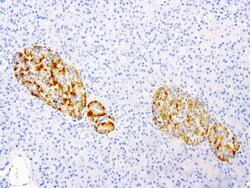

- Main image

- Experimental details

- Immunohistochemical staining of paraffin-embedded human pancreas using anti-VSNL1 clone UMAB115 mouse monoclonal antibody (UM800034) at 1:200 with Polink2 Broad HRP DAB detection kit; heat-induced epitope retrieval with GBI Citrate pH6.0 HIER buffer using